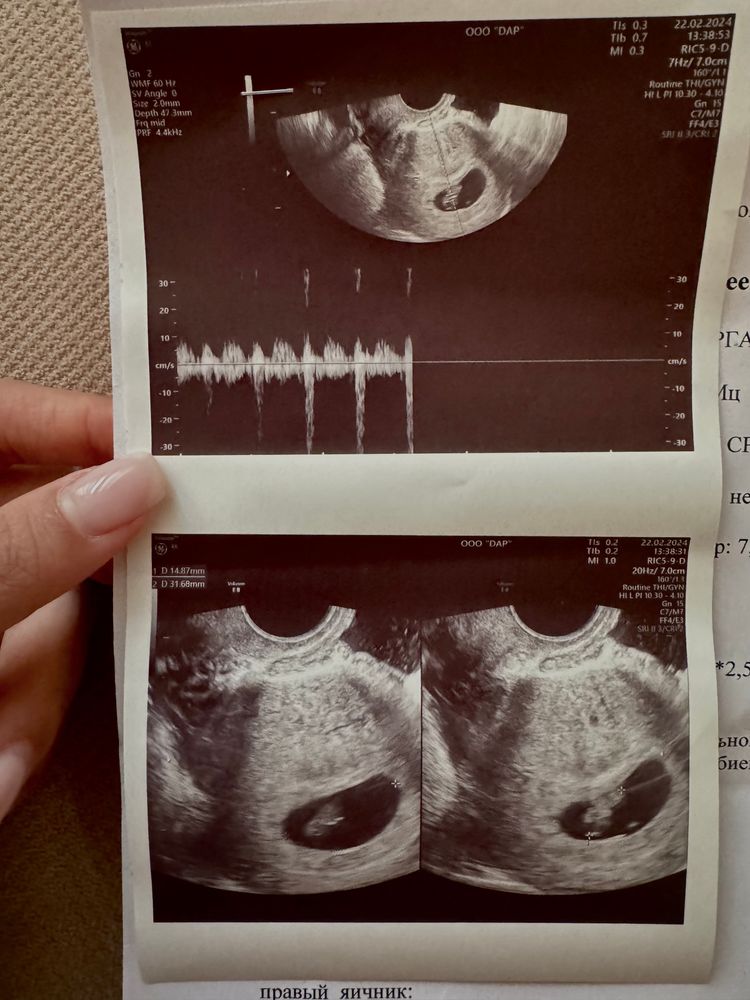

Сегодня нам ровно 8 недель❤️

КТР 15мм, ПЯ 22*25*31мм, ЖМ до 4*4*5мм, ЖТ до 23мм диаметром.